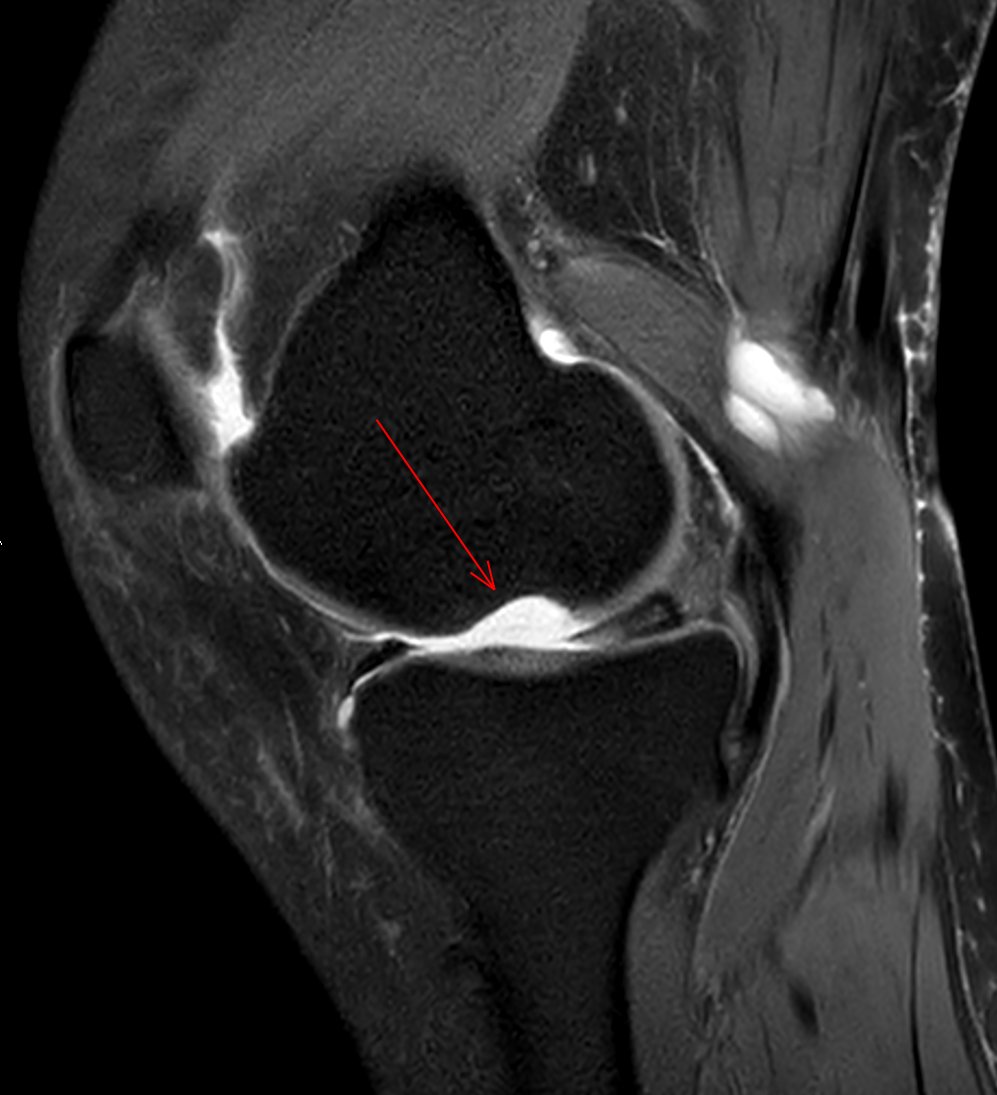

JuanMiranda@themskarchive·

19/11/2025. 🦵 55 y/o woman with knee pain. FSPD #MRI, 1 year apart: 📍 Baseline: large osteochondral defect in the lateral aspect of the medial femoral condyle 🔧 Arthroscopic microperforations (microfracture) ✨ Follow-up: defect filled with fibrocartilage-like tissue👀 #MSK

JuanMiranda tweet mediaJuanMiranda tweet mediaJuanMiranda tweet mediaJuanMiranda tweet media